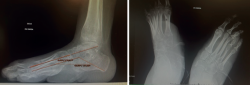

Se trata de una paciente de 34 años en seguimiento en consultas externas por pie zambo derecho congénito. Presenta un tobillo, mediopié y antepié rígidos, un pie equino, varo, aducto y supinado rígido (Figura 1), además de anestesia sensitiva (a consecuencia de lipomeningocele).

Figura 1. Pie zambo derecho con deformidad en equino, varo aducto y supinado.